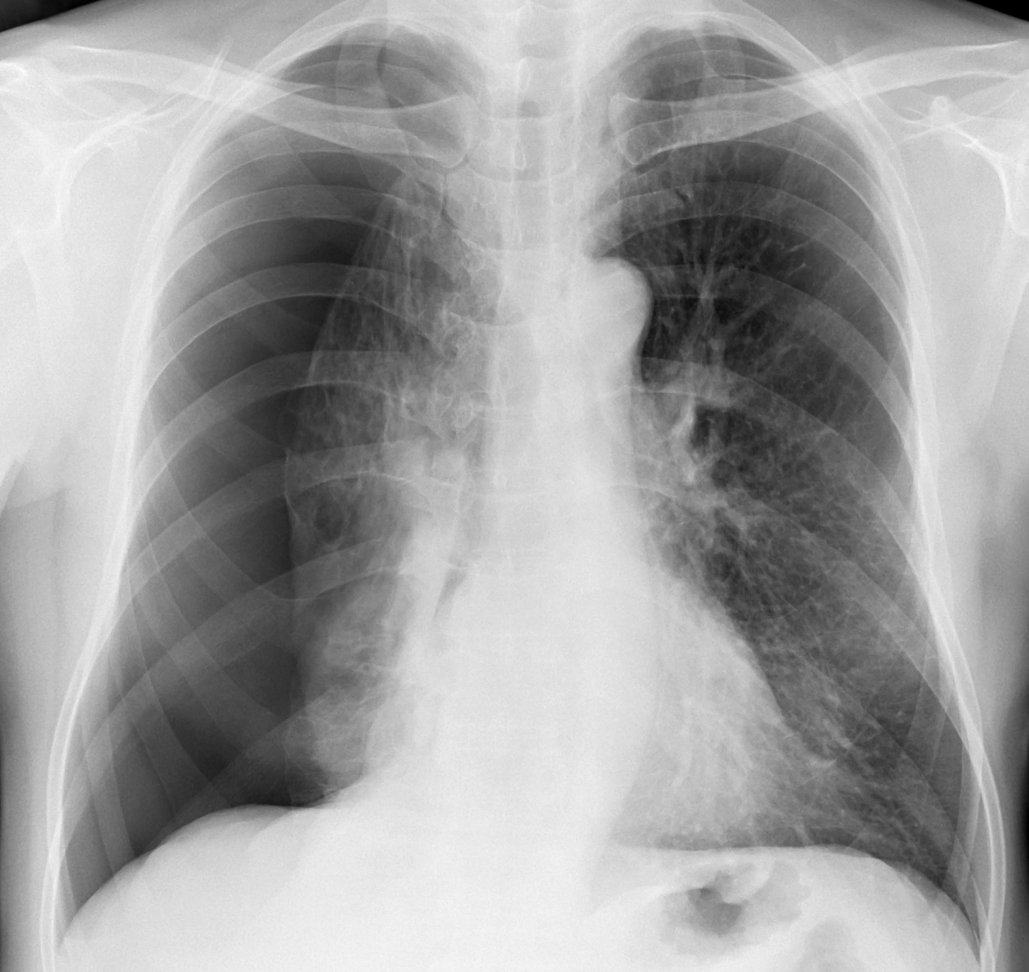

気胸とは、 「胸腔内に空気が貯留し、 肺が虚脱した状態」 を指す。 治療方針は原因の臨床的評価や、 患者の症状、 気胸のサイズによって決定されるため、 迅速な診断と病態の理解が極めて重要である¹。

立位胸部X線写真で、 虚脱した肺尖と鎖骨の位置関係で 「軽度・中等度・高度」 に分類

軽度 (Mild) 虚脱した肺の頂上部 (肺尖部) が、 鎖骨と同じかそれよりも高い位置にある状態

中等度 (Moderate) 軽度と高度の中間の虚脱度。 肺尖が鎖骨より下に位置する状態

高度 (Severe) 肺が完全につぶれている (完全虚脱)、 またはそれに近い状態